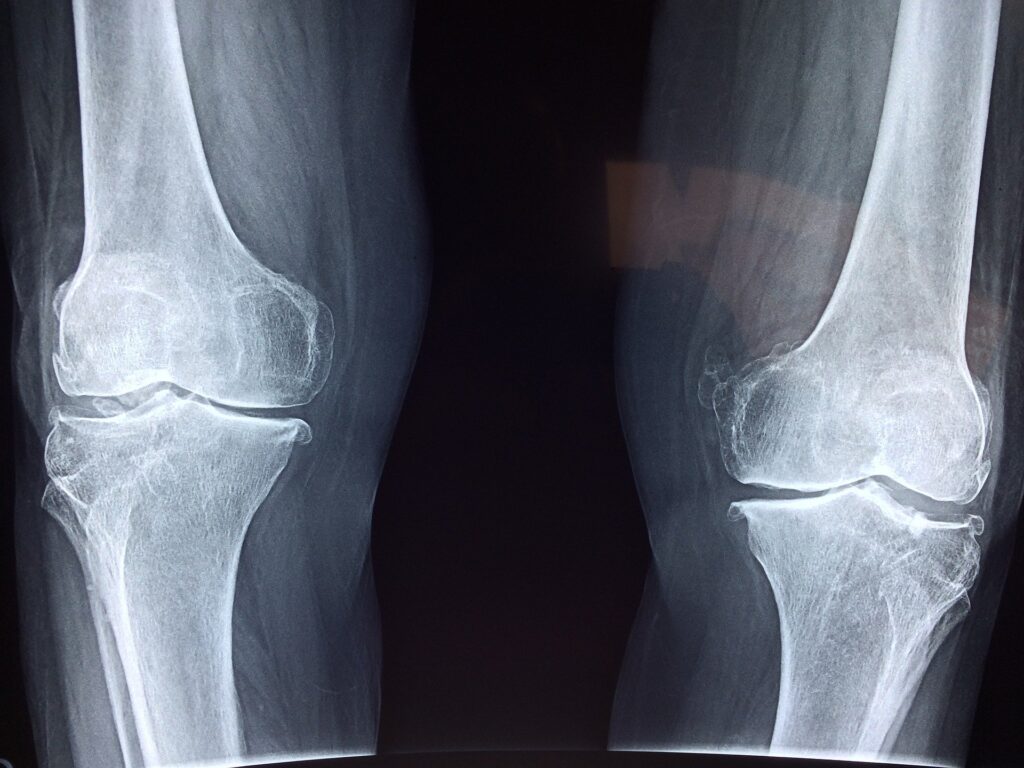

Health X on Twitter "Knee pain caused by osteoarthritis is a common Osteoarthritis Is Disability Arthritis causes more than just pain. It is also one of the most common causes of physical disability among adults. A disability is a condition that limits your typical movements,. Osteoarthritis is a degenerative joint disease that happens when the tissues that cushion the ends of the bones within the joints break down over time. So, if your osteoarthritis severely. Osteoarthritis Is Disability.

Can I get Social Security Disability for my osteoarthritis of the knee Osteoarthritis Is Disability Osteoarthritis is a degenerative joint disease that happens when the tissues that cushion the ends of the bones within the joints break down over time. Osteoarthritis may be considered a disability if it significantly impacts a person’s ability to perform major life activities, including work. With an ageing and increasingly obese population, this syndrome is becoming even more prevalent than. Osteoarthritis Is Disability.

Health X on Twitter "Knee pain caused by osteoarthritis is a common Osteoarthritis Is Disability It is also one of the most common causes of physical disability among adults. Osteoarthritis is a degenerative joint disease that happens when the tissues that cushion the ends of the bones within the joints break down over time. Osteoarthritis is a leading cause of disability and source of societal cost in older adults. Under the americans with disabilities act. Osteoarthritis Is Disability.